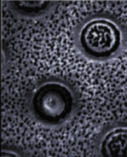

Called a “liver bioreactor,” the apparatus consists of a chip of spongelike silicon with pores just 2 to 1,500 nanometers wide. The research team, from the University of California, San Diego (UCSD), used electrochemistry to etch the pores and then circuit-making techniques to add 15-micron-wide wells, each just big enough to house a rat liver cell.

The liver’s primary cells, hepatocytes, are notoriously hard to culture. But when grown in the bioreactors, thousands of the cells functioned normally throughout a 2-week trial, the researchers reported last week in San Diego at a meeting of the American Chemical Society.

Pores of certain sizes provide a texture on which cells thrive, graduate student Vicki Chin found. “It’s kind of like the Goldilocks principle,” says chemist Michael J. Sailor, a member of the team. “Some of these holes are too big, some too small, and some are just right.”